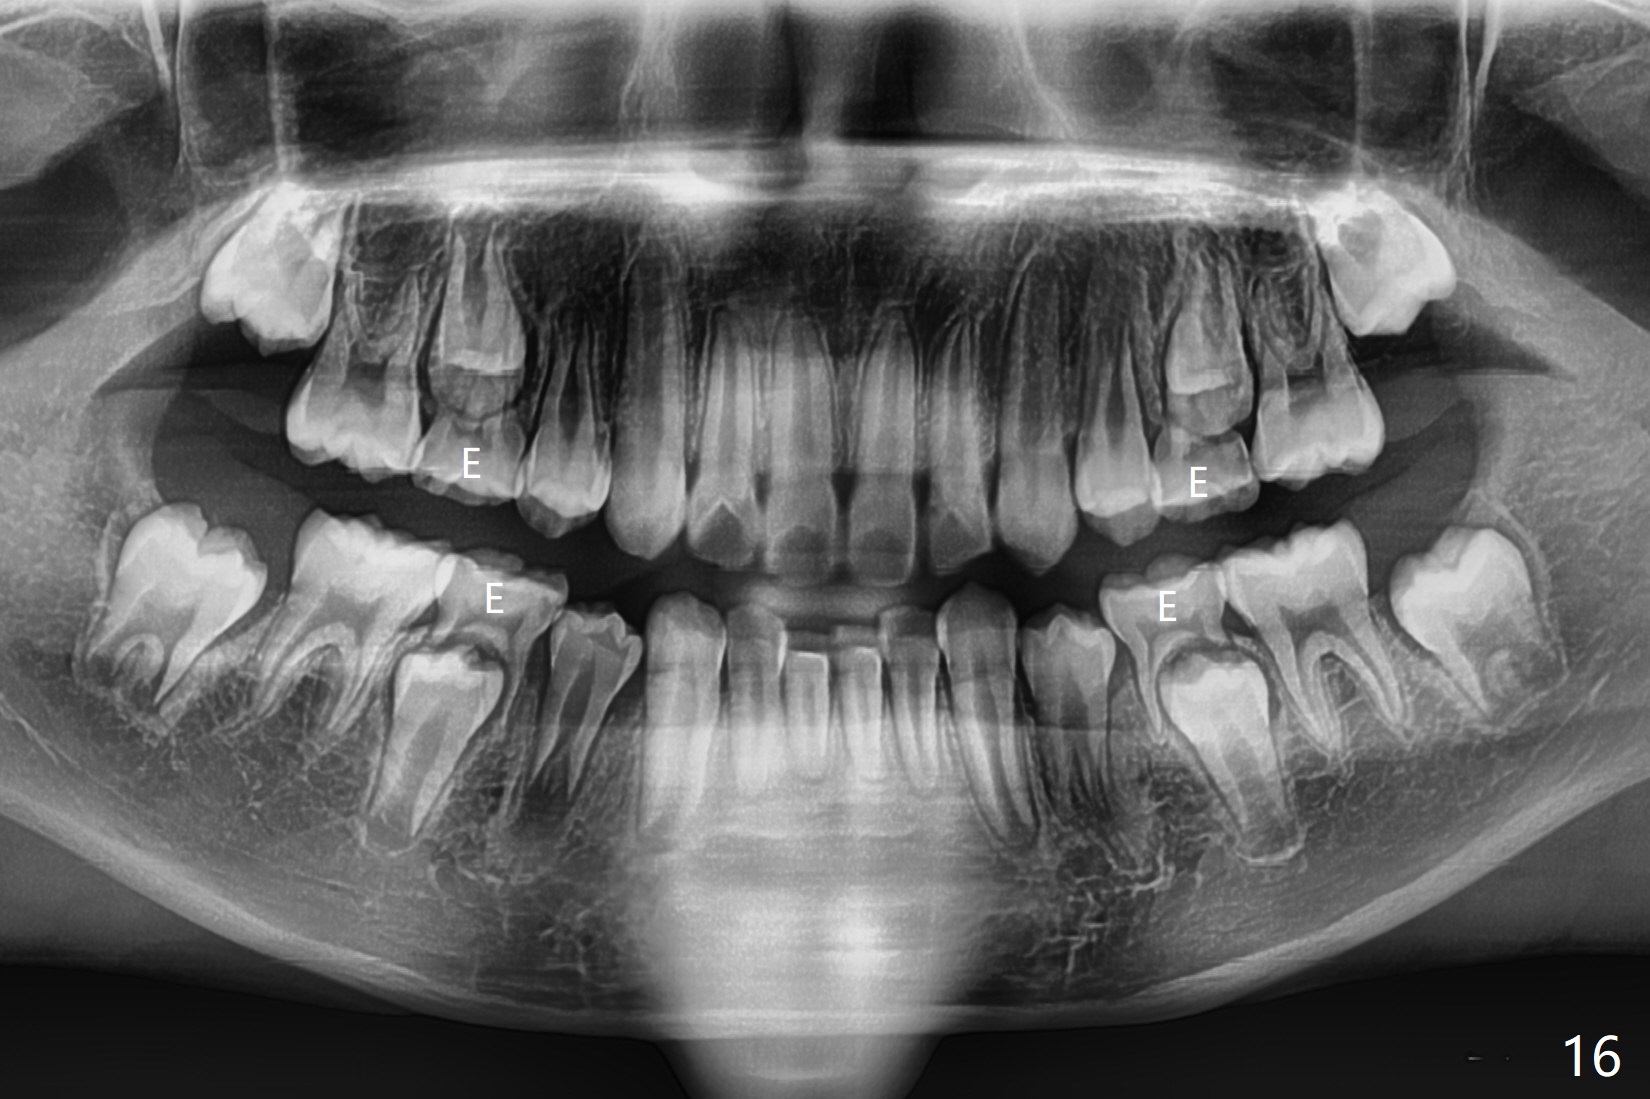

The mother of a 10-year-7-month old man requests treatment for the crowding lower incisors (Fig.14). The canines and molars are Class II by a half of a tooth (Fig.7,9,10,12). The dentition is mixed with E retention (Fig.13,14,16). Orthodontic treatment will start before E exfoliation for alignment and establishment of Class I occlusion as much as possible by distalizing U6s. Fine adjustment for intedigitation will be made when E exfoliate.